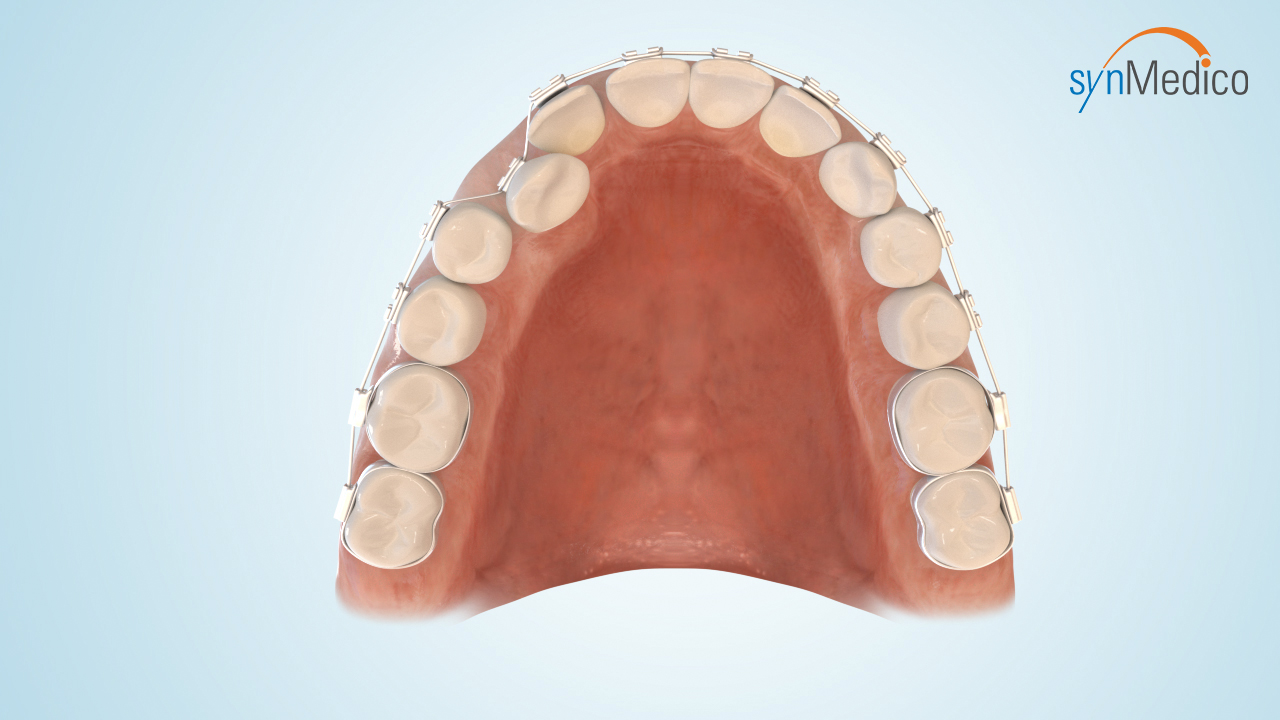

Freilegung von Zähnen

Gelegentlich verbleiben Zähne in der Wachstumsphase im Kiefer, da eine Blockade durch Nachbarzähne den Durchtritt verhindert. Durch eine kombinierte Behandlung mit den Techniken der Kieferorthopäde und der Kieferchirurgie können solche Zähne in die Zahnreihe eingestellt werden.